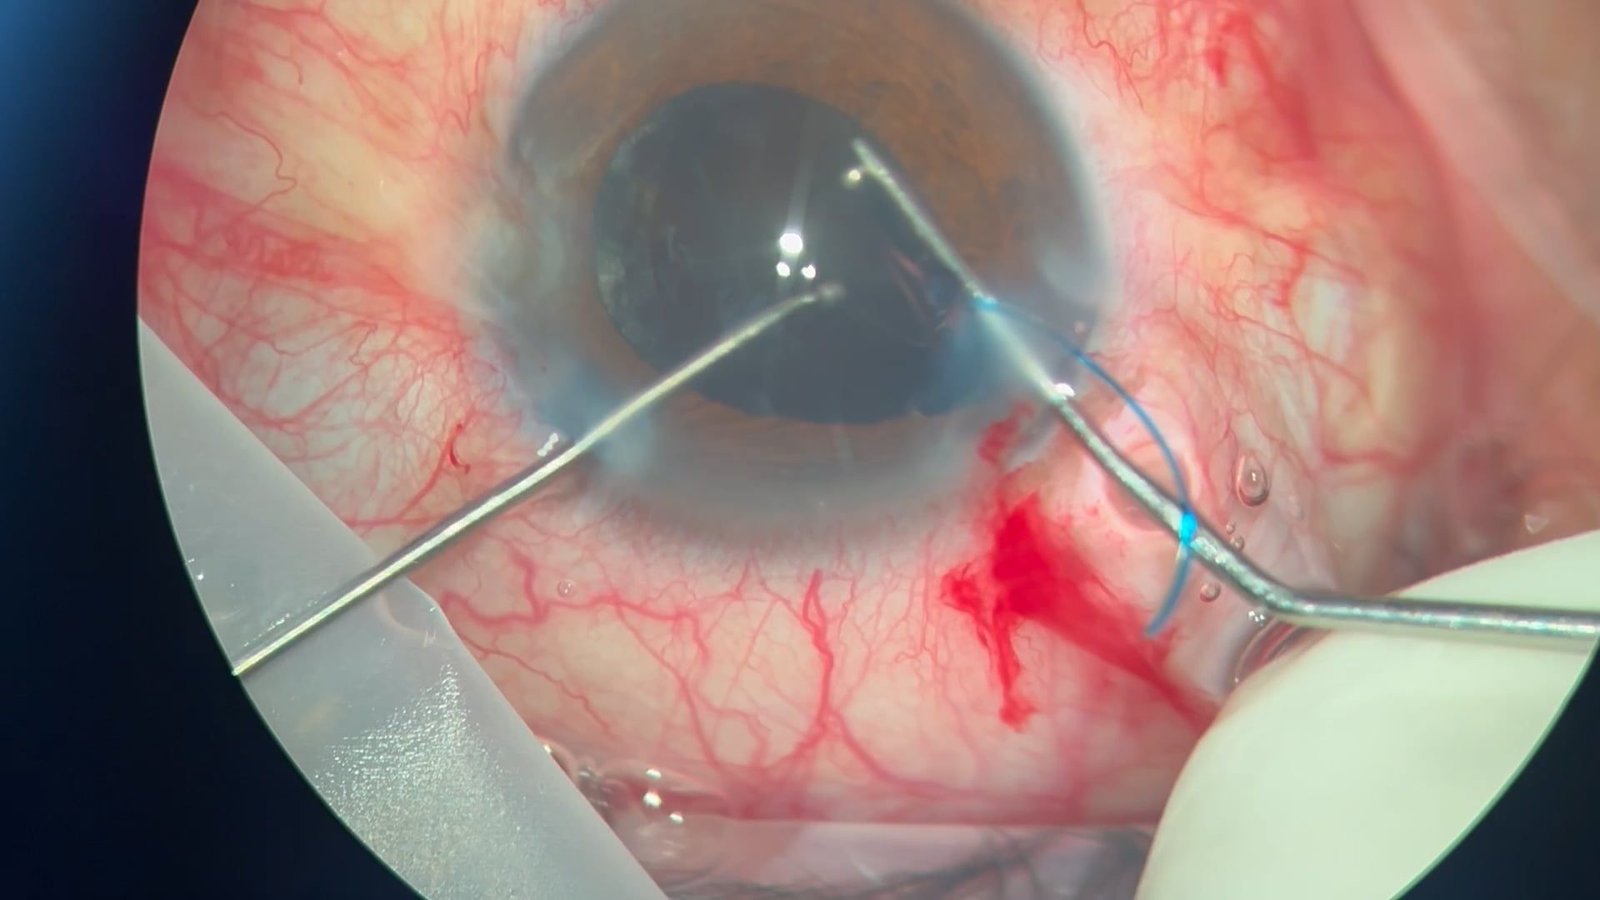

Una faco intensamente azul

Valentina Aranda Barois